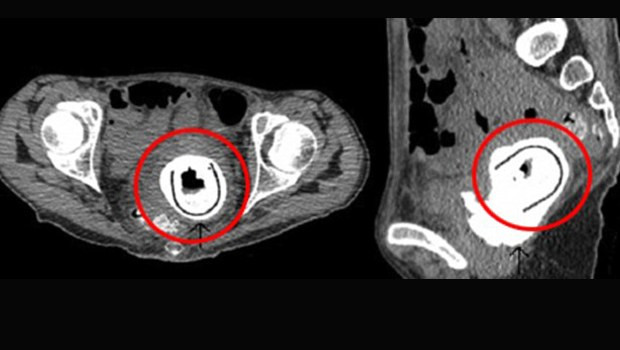

İngiltere’de aşırı kilo kaybı ve halsizlik şikayetiyle hastaneye giden 38 yaşındaki bir kadının vajinasından idrar kesesine doğru çıkan yabancı cisim doktorları şaşkına çevirdi.

Abone olYapılan ameliyat sonrası kadının vajinasından yaklaşık 11 santimerelik bir seks oyuncağı çıkarıldı.

Ameliyat sonrası “vezikovajinal fistül” (idrarın vajinaya sızması) ve “obstrüktif üropati” (idrarın böbreklere geri dönmesi) hastalıklarına yakalandığı anlaşılan kadın tedavi altına alındı.